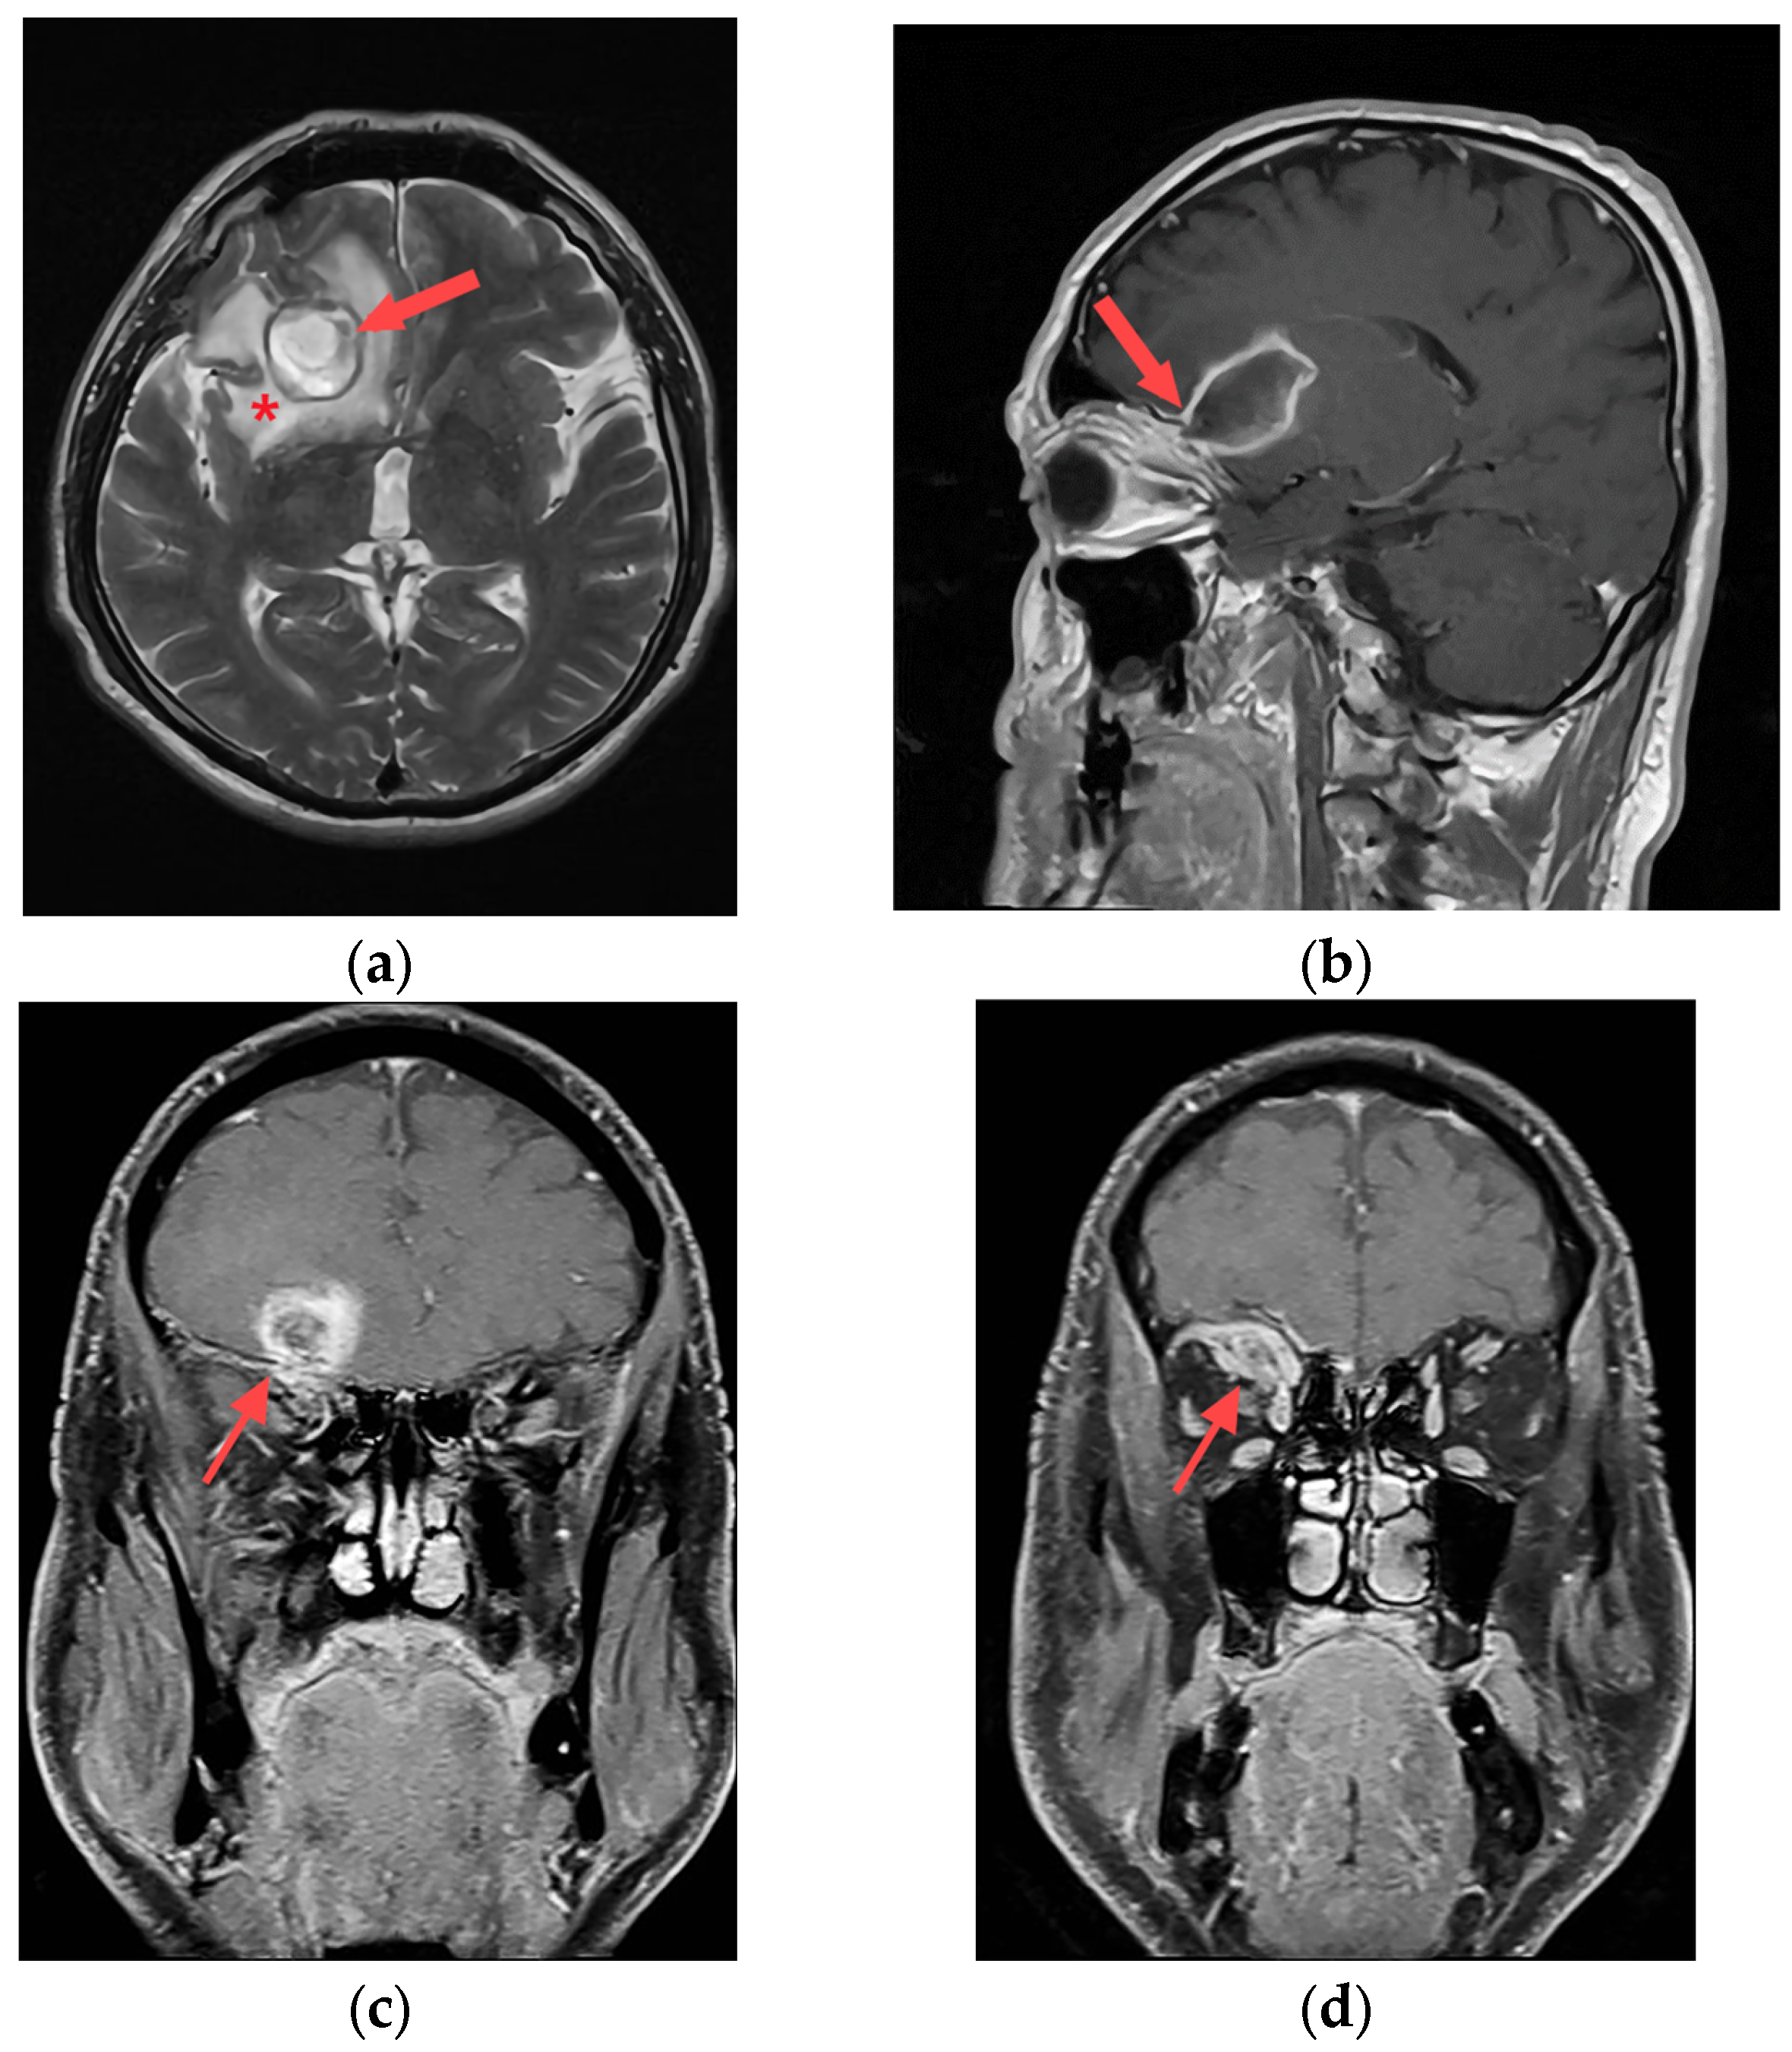

To investigate the underlying cause of the patient’s symptoms, magnetic resonance imaging (MRI) was performed using Siemens Magnetom Avanto 1.5 T in Erlangen, Germany. The MRI scan revealed a significant abnormality in the right frontal lobe, depicted in Figure 1a,b. Figure 1a displayed the presence of an abscess within the right frontal lobe. Additionally, periabscess edema and displacement of midline structures were evident, indicating compression of the surrounding tissue. Figure 1b illustrates the abscess attached to the orbital roof, and the trajectory of the injury from approximately one month earlier. The foreign body’s trajectory, which penetrated the upper part of the upper eyelid conjunctival region, followed a periosteal path along the orbital roof, ultimately reaching the posterior part of the orbital roof within the frontal lobe region, as shown in Figure 1c. An ophthalmologist confirmed the diagnosis of orbital cellulitis, as depicted in Figure 1d.

Figure 1.

Preoperative MRI; (a) axial T2W slice with abscess in right frontal lobe (red arrow) and perifocal edema (*); (b) sagittal T1W slice with attachment of abscess to roof of orbit (red arrow); (c) coronal T1W slice with position of brain abscess and roof penetration (red arrow); (d) coronal T1W slice with intraorbital infective process presence (red arrow).